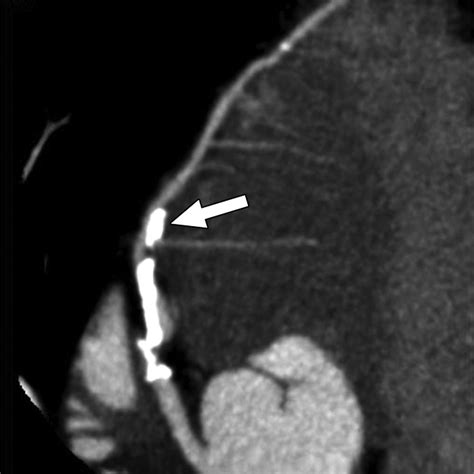

Cardiac CT Angiography A non-invasive way to view the coronary arteries using contrast dye.

• Percutaneous Coronary Intervention (PCI): Commonly known as angioplasty, this procedure involves threading a balloon-tipped catheter to the site of the Left Circumflex Artery blockage, inflating it to open the vessel, and often placing a stent to keep it open.